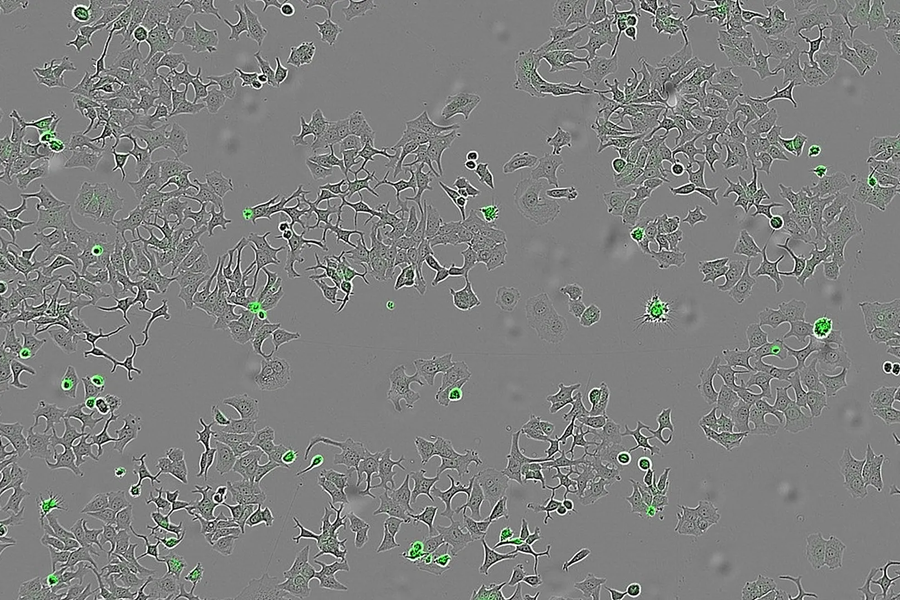

‏Các nhà khoa học Tây Ban Nha tìm ra protein “diệt” ung thư‏

‏Phương pháp mới này đã được thử nghiệm trên các tế bào ung thư vú, đại tràng và tuyến tụy.‏